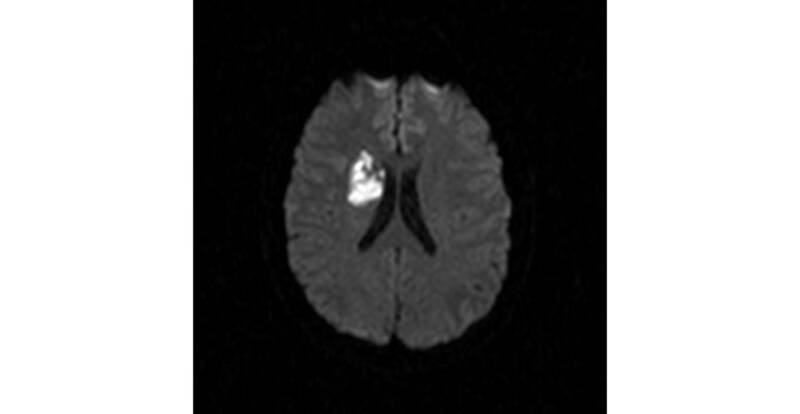

Die häufigste Ursache für einen Schlaganfall sind Gefäßverschlüsse oder -verengungen der hirnversorgenden Arterien durch Blutgerinnsel. Je früher der Patient neurologisch begutachtet und untersucht wird, desto früher kann die Akuttherapie zur medikamentösen Auflösung dieses Blutgerinnsels verabreicht werden. In den letzten Jahren wird neuerdings in speziellen Zentren versucht, rasch ein solches Gerinnsel direkt aus dem betroffenen Gefäß mittels eines Retrievers – einer Art „Schraubenzieher“ – zu entfernen, um damit die Prognose der Patienten zu verbessern.